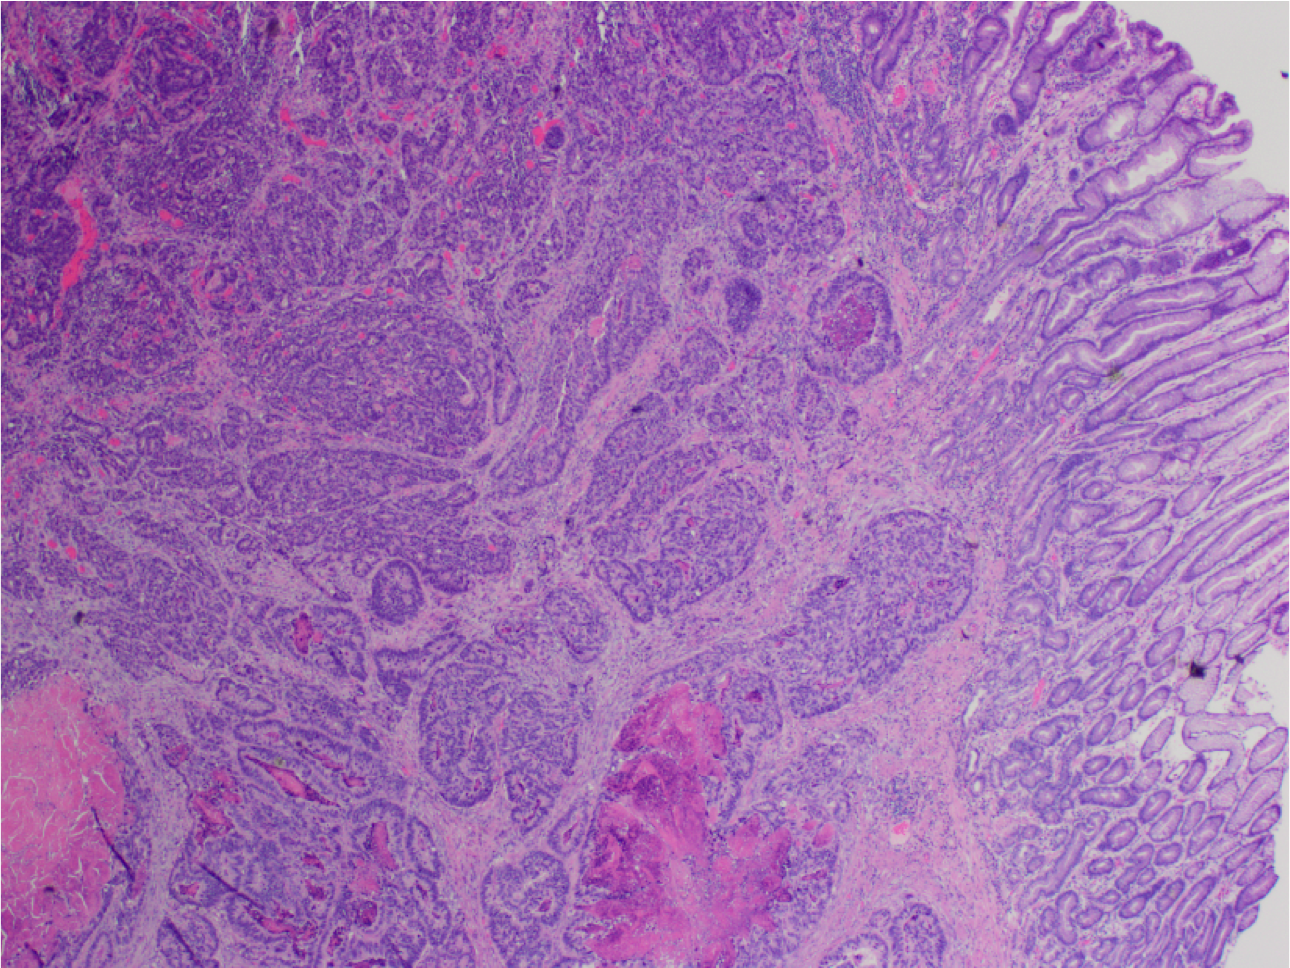

What’s this?

Gastric adenocarcinoma

Infiltrative growth of complex glands, which may contain pink necrotic debri (as in this case). Compare to normal crypts on the right.